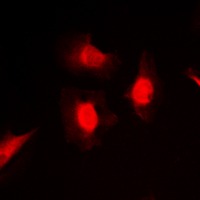

| Reactivity | Human,Mouse,Rat |

| Verified Activity | 1. Western blot analysis of PKC iota/zeta (phospho-Thr412/410) expression in MCF7 TNFa-treated, NIH3T3 LPS-treated, PC12 UV-treated whole cell lysates. 2. Immunohistochemical analysis of PKC iota/zeta (phospho-Thr412/410) staining in human breast cancer formalin fixed paraffin embedded tissue section. The section was then incubated with the antibody at room temperature and detected using an HRP conjugated compact polymer system. DAB was used as the chromogen. The section was then counterstained with haematoxylin and mounted with DPX. 3. Immunofluorescent analysis of PKC iota/zeta (phospho-Thr412/410) staining in MCF7 cells. Formalin-fixed cells were permeabilized with 0.1% Triton X-100 in TBS for 5-10 minutes and blocked with 3% BSA-PBS for 30 minutes at room temperature. Cells were probed with the primary antibody in 3% BSA-PBS and incubated overnight at 4 C in a hidified chamber. Cells were washed with PBST and incubated with a DyLight 594-conjugated secondary antibody (red) in PBS at room temperature in the dark. ![]() ![]() ![]() |